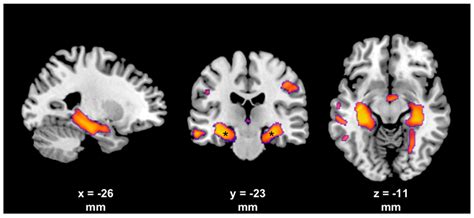

Scientific illustration of a nerve cell